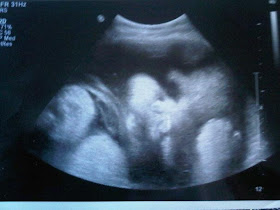

2nd And 3rd Trimester Ultrasound Scanning

Ultrasound Scan Fetal Growth Scan Patient Information Brochures